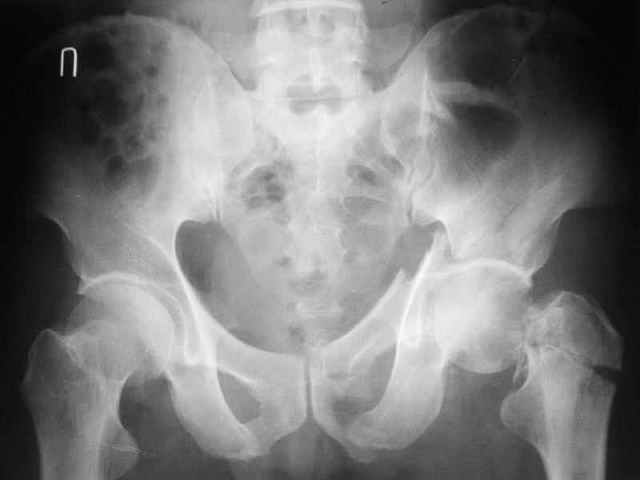

Больной 18 мая 2003 года в автоаварии получил перелом левой вертлужной впадины, вывих бедра. Госпитализирован в один из стационаров области.Вывих вправлен. В последствии бедро вывихивалось еще дважды. На консультацию был представлен снимок от 19.05.03г., больной переведен к нам 3.06.03г. Снимок при поступлении - перелом впадины, задне-верхний вывих бедра. 05.06.2003 г. выполнено открытое вправление вывиха левого бедра и остеосинтез стенки вертлужной впадины двумя винтами. Послеоперационный период без осложнений. Объем движений в левом тазобедренном суставе восстановился полностью. Выписан на амбулаторное лечение в удовлетворительном состоянии с рекомендациями 3 месяца ходить на костылях без нагрузки на оперированную конечность. На контрольных рентгенограммах левого тазобедренного сустава 13.10.2003 г. - признаки консолидации перелома; плотность, форма головки и состояние суставных поверхностей удовлетворительные. Разрешена дозированная осевая нагрузка, на конечность с использованием дополнительной опоры. 19.12.2003 г. больной обратился с жалобами на боли в левом тазобедренном суставе. На рентгенограммах левого тазобедренного сустава 19.12.2003 г., 20.02.04г. - асептичекий некроз головки бедра. 5.04.04г. - эндопротез. Сейчас ходит без трости, не хромает. Особенность эндопротезирования - при удалении винтов прослежена линия перелома заднего края впадины и предложено установить чашку несколько меньшего диаметра, чтобы она была покрыта несломанной частью.